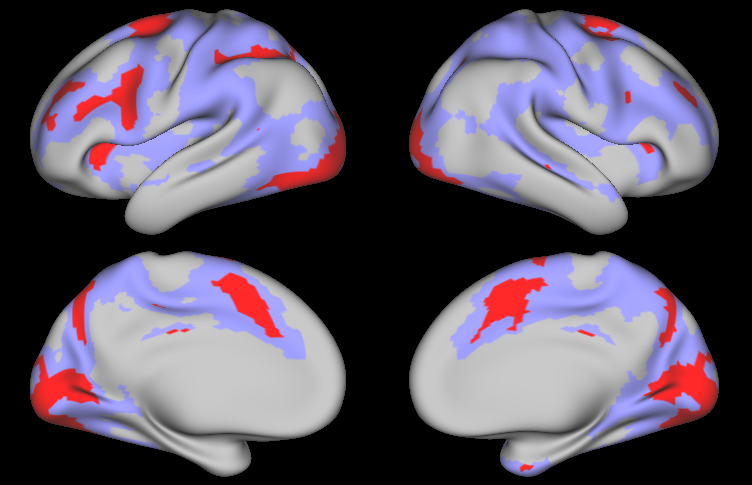

The left and right hemisphere each contain 32,492 surface vertices, including approximately 2,700 missing values in the medial wall. To reduce the computational burden while maintaining high spatial resolution, we used the Connectome Workbench to resample each hemisphere to approximately 6,000 vertices (Marcus et al. 2011). A spherical mesh was created based on the radial coordinates of the locations excluding missing values in the medial wall, resulting in a mesh with approximately 5,300 vertices. Figure LABEL:fig:app:mesh displays the lateral (external) and medial (internal) surfaces of the spherical mesh for each hemisphere. After model fitting, coefficient estimates and posterior probabilities for the 32,492 vertices for each hemisphere were obtained by projecting back to the original resolution using the Connectome Workbench tools.

Left Hemisphere Right Hemisphere

[Uncaptioned image]       [Uncaptioned image]

Figure LABEL:fig:app:beta_subj displays the Bayesian estimates of activation amplitude (posterior means) for the visual cue and tongue tasks, along with the classical GLM estimates, for one randomly selected subject. The remaining tasks are shown in Appendix C. Both sets of estimates are noisy, due to the high levels of noise in fMRI data and relatively short duration of the tasks performed for each individual subject (303030 seconds for the visual cue; 242424 seconds for the tongue task); however, the Bayesian estimates are substantially smoother than the classical estimates, even though the data was smoothed prior to fitting the classical GLM but not the Bayesian GLM. Figure LABEL:fig:app:beta displays group-level estimates of activation amplitude based on the classical and Bayesian GLM approaches. For the Bayesian GLM, the results using the joint modeling approach and the two-level modeling approach with the sampling method described in Section 3.1 are both displayed. In both the subject-level and group-level estimates, the activation fields for each task are generally as expected: during the visual cue, the visual and orbitofrontal (decision making) regions are highly active, while the somatomotor (motor planning) region is activated to a lesser degree; during the tongue movement task, the area of the motor cortex associated with the tongue shows a strong degree of activation; and the remaining motor tasks activate the expected areas of the motor cortex (see Figures S4 and S5 in Appendix C). Compared with the classical GLM, the Bayesian GLM results in smoother estimates of activation, as it accounts for dependence in the degree of activation between neighboring locations. As hypothesized, the two-level modeling approach tends to result in somewhat oversmoothed estimates, compared with the joint modeling approach.

Figure LABEL:fig:app99 shows the regions of activation identified by thresholding the joint PPM excursion function for each task, along with those identified through the classical GLM with FDR and FWER correction, using significance level 0.010.010.01 in each method. For the Bayesian GLM, regions of activation at activation threshold γ=0𝛾0\gamma=0 are shown in purple, while those at γ=0.027𝛾0.027\gamma=0.027, corresponding to 1%percent11\% of the global baseline signal, are shown in red. Several effects are clearly notable. First, the areas of activation based on controlling the FWER in the classical GLM are very conservative. This is a well-known issue with this approach that worsens as the number of locations increases, which is likely why FWER correction produces reasonable results in the simulation study but very conservative results on real fMRI data. FDR control results in significantly larger areas of activation, reflecting an increase in power while maintaining a known degree of false positive control. Second, the areas of activation based on γ=0𝛾0\gamma=0 in the Bayesian GLM are similar to those based on FDR control in the classical GLM, but are smoother and somewhat larger. This likely reflects an increase in power resulting from incorporating spatial dependencies in the Bayesian GLM, as observed in our simulation study. Third, compared with the joint model, the areas of activation based on the Bayesian two-level model are smoother but similar in size. This illustrates that while the two-level approach tends to result in somewhat oversmoothed estimates, the sampling method described in Section 3.1 is able to appropriately account for uncertainty in the subject-level estimates when fitting the group-level model. Finally, the increased power in the joint PPM results in widespread areas of activation based on γ=0𝛾0\gamma=0, while the more biologically meaningful threshold of γ=0.027𝛾0.027\gamma=0.027 (1%percent11\% of the baseline signal) results in more conservative areas of activation that correspond well to the highly activated areas shown in yellow in Figure LABEL:fig:app:beta.

These results illustrate the benefits of using a Bayesian framework to account for spatial dependencies in fMRI task activation studies. Compared with the traditional analysis techniques, the proposed Bayesian GLM approach results in smoother estimates of activation for individual subjects and groups of subjects, smoother active regions, and greater power to detect areas of activation, particularly more subtle activations.